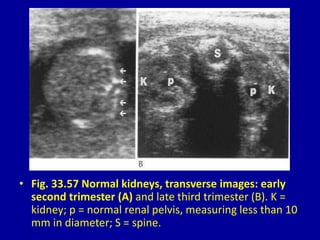

• Fig. 33.57 Normal kidneys, transverse images: early

second trimester (A) and late third trimester (B). K =

kidney; p = normal renal pelvis, measuring less than 10

mm in diameter; S = spine.

• Fig. 33.57Normal kidneys, transverse images: early second trimester (A) and late third trimester (B). K = kidney; p = normal renal pelvis, measuring less than 10 mm in diameter; S = spine.